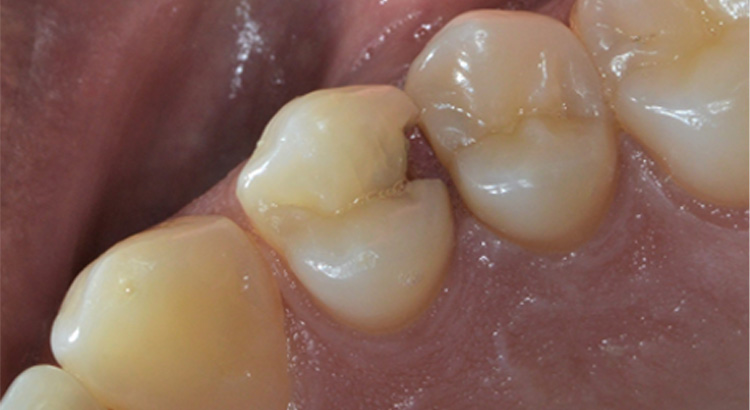

Conservativa

Il paziente non sapeva di avere una carie estesa tra i due premolari. Fortunatamente non procurava dolore e si è potuto salvare il dente con una ricostruzione in materiale composito e ristabilire il corretto rapporto tra i due denti.